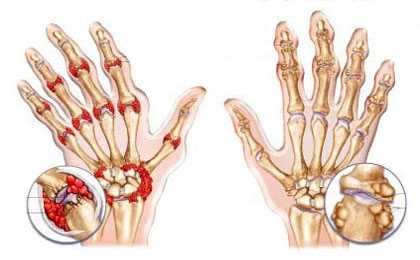

Что делать если болят суставы правой и левой кистей рук? Причиной может стать ревматоидный артрит. Это хроническое аутоиммунное заболевание, при котором организм воспринимает собственные клетки за чужеродные и начинает их уничтожать. Поражаются кости, хрящи или связки. Отличительным признаком заболевания является симметричность, т.е. боль проявляется в обеих кистях одновременно. Может возникать в любом возрасте.

Разрушение тканей приводит к воспалительному процессу. Появляется тупая ноющая боль, суставы отекают, кожные покровы на руках краснеют. Болезненные ощущения могут быть постоянными или периодическими, появляется скованность движений после сна. Облегчению болевого спазма способствует физическая разминка.В тяжелых формах развивается веретенообразная форма кистей. В области суставов характерно увеличение температуры – эффект «горячих суставов». Суставы начинают деформироваться и выворачиваться.

В большинстве случаев это системное воспалительное заболевание начинается с болей в кистях рук, а именно в суставах у основания пальцев и лучезапястных сочленениях. Поражение симметричное, боли беспокоят больше в утренние часы, сочетаясь со скованностью движений. Также характерен стойкий отек, горячие кожные покровы. На более поздней стадии на кистях появляются плотные ревматоидные узелки, деформации пальцев по типу «лебединой шеи», «бутоньерки». Лечение ревматоидного артрита заключается в назначении базисных препаратов (метотрексат), гормонов (преднизолон), противовоспалительных средств и применении местной терапии (физиопроцедуры, ЛФК, массаж).